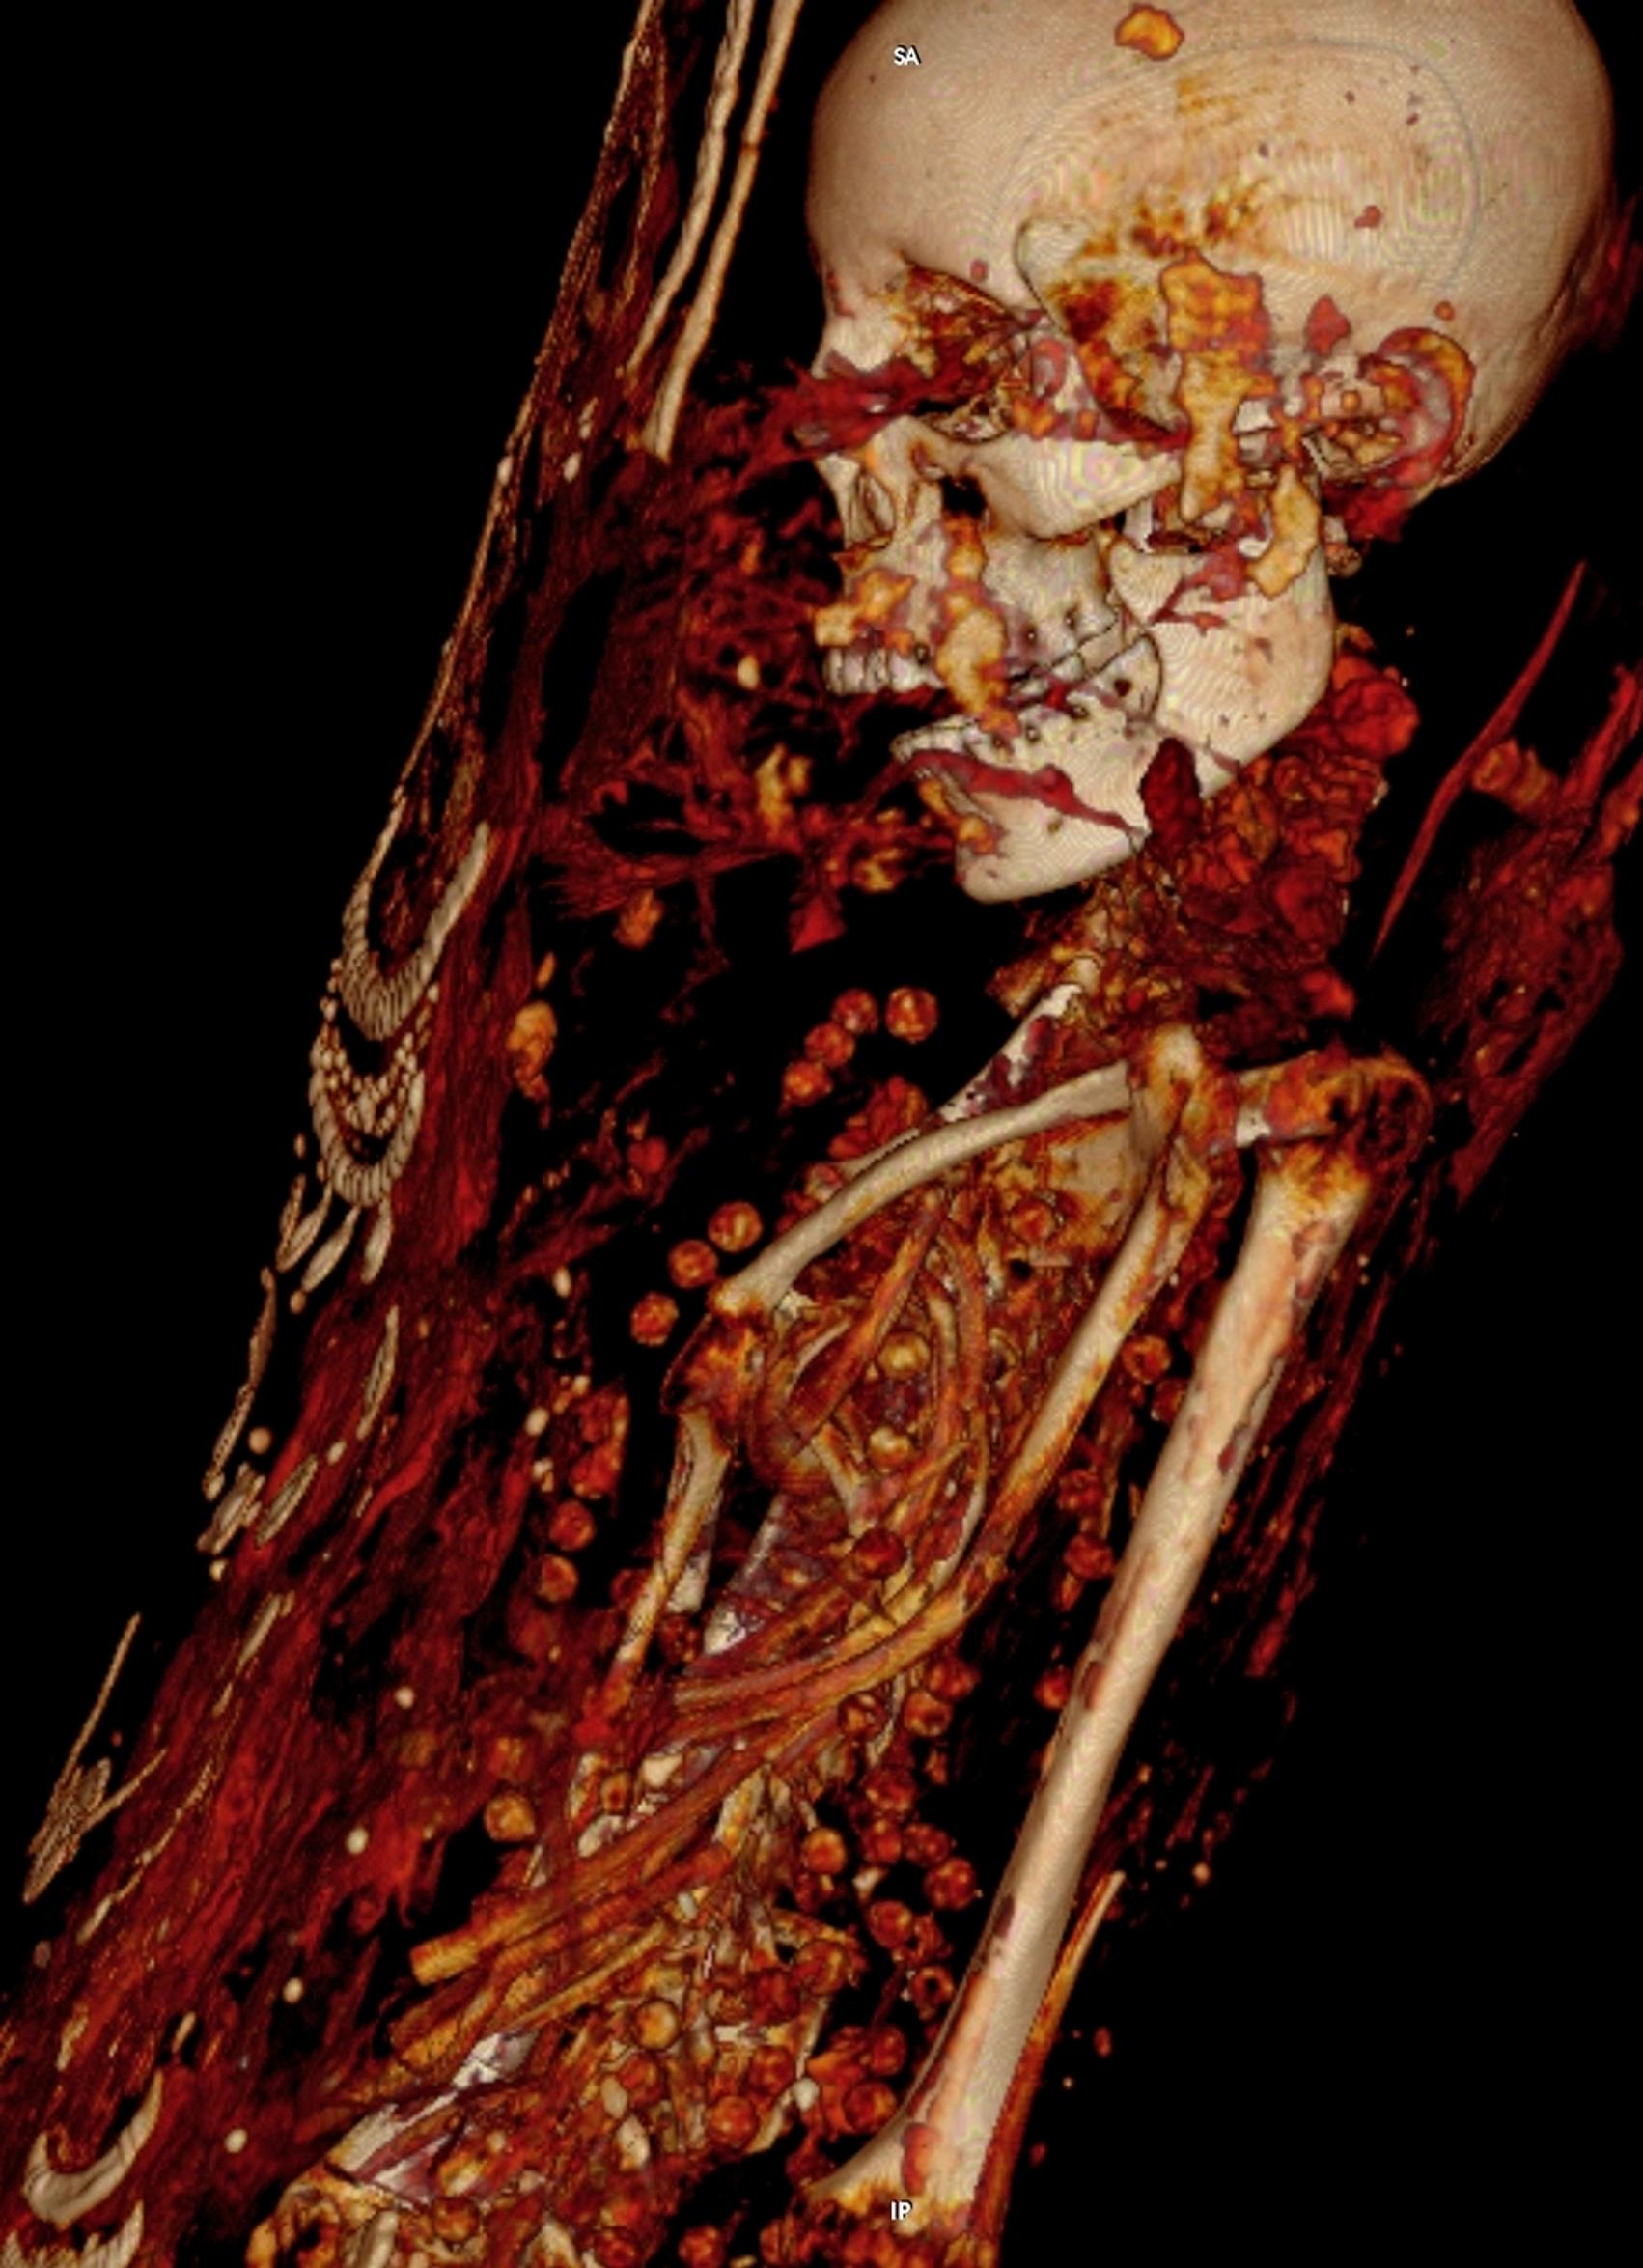

Tietokonekuvaus paljastaa, millaisessa kunnossa muumiot olivat eläessään. Naisella ja tytöllä on useita kaulakoruja ja tytöllä hiusneula. Muumiot ajoitettiin roomalaiselle kaudelle 30 eaa.–395 jaa.

Kaksi yli 400 vuotta sitten löydettyä muumiota paljastivat salojaan, kun arkeologit pääsivät tutkimaan niitä tietokonekerroskuvauksella eli CT-kuvauksella.

Muumiot vaihtoivat useaan otteeseen omistajaa ja päätyivät lopulta Saksaan Dresdenin taidekokoelmaan, jossa ne röntgenkuvattiin 1980-luvulla. Nyt tehdyt CT-kuvaukset paljastivat muumioista uusia asioita, kertoo Live Science -lehti.

Ilmeni, että 25–30-vuotiaana kuollut mies oli pituudeltaan noin 164 senttiä. Miehen katkenneiden luiden syyksi epäillään sitä, että joku olisi poistanut muumion kääreet sen löydön yhteydessä.

Nainen, joka oli kuollut 30–40-vuotiaana, oli 151-senttinen. Hänen toisessa polvessaan oli pitkälle edennyt nivelreuma.

17–19-vuotiaana kuolleen tytön selkärangasta taas löytyi kasvain. Ainakin tyttö oli haudattu sisäelimineen. Naisella ja tytöllä on useita kaulakoruja ja tytöllä hiusneula. Muumiot ajoitettiin roomalaiselle kaudelle 30 eaa.–395 jaa.